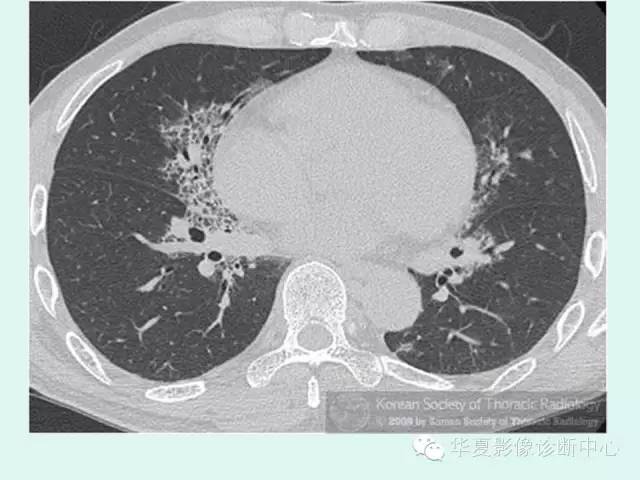

【病例】肺泡蛋白沉积症1例CT影像表现